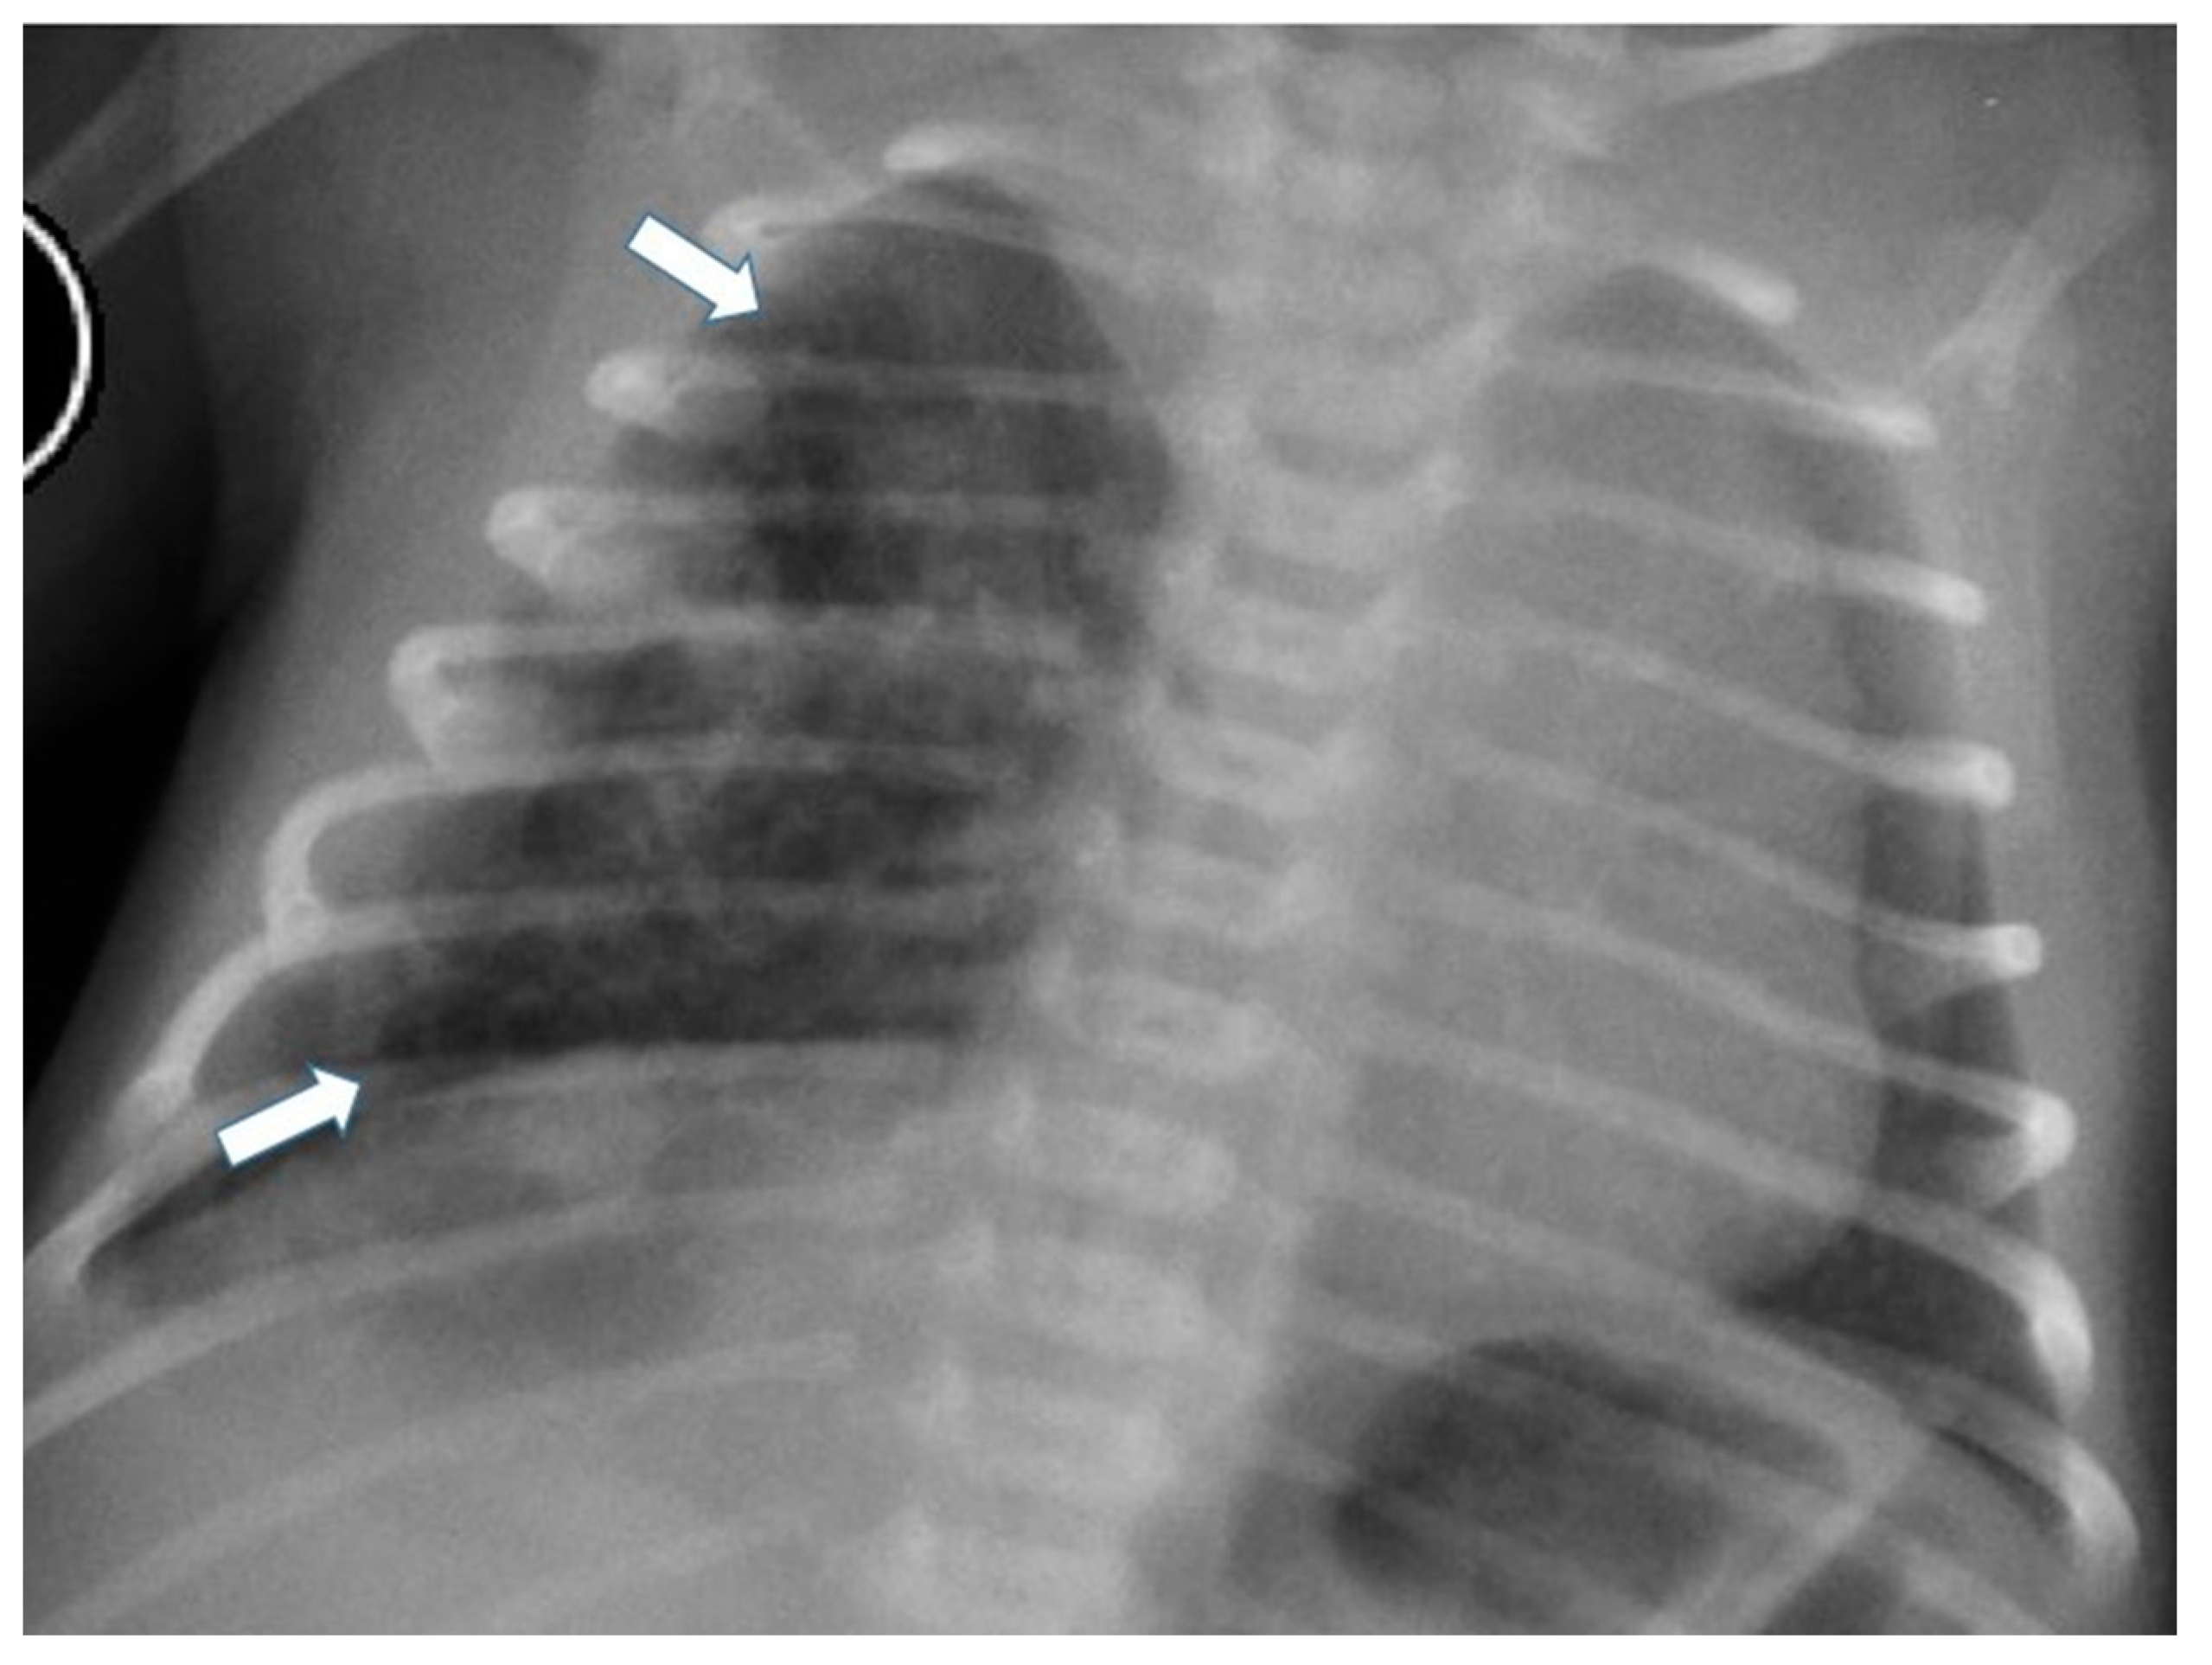

3.4.2. Congenital Pulmonary Airway Malformations

3.4.3. Congenital Lobar Hyperinflation

3.4.4. Congenital Bronchial Atresia

3.4.5. Bronchogenic Cysts